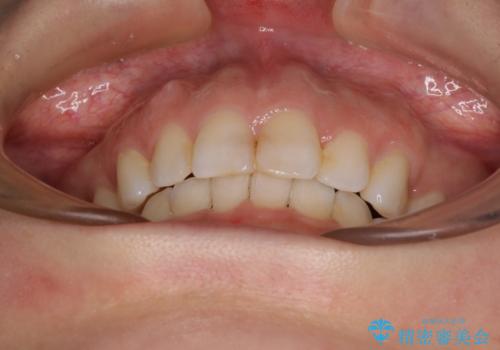

出っ歯と咬み合わせを改善 ワイヤー装置の抜歯矯正

- 口元の閉じにくさと、奥歯の咬み合わせを気にして来院された患者様です。

奥歯の咬み合わせ改善には1年ほどの期間と処置中の噛みにくさを強いることとなりましたが、抜歯後はスムーズに治療を完了させることができました。

歯ぎしりの際に奥歯が干渉していた咬み合わせも理想的な状態に改善できました。